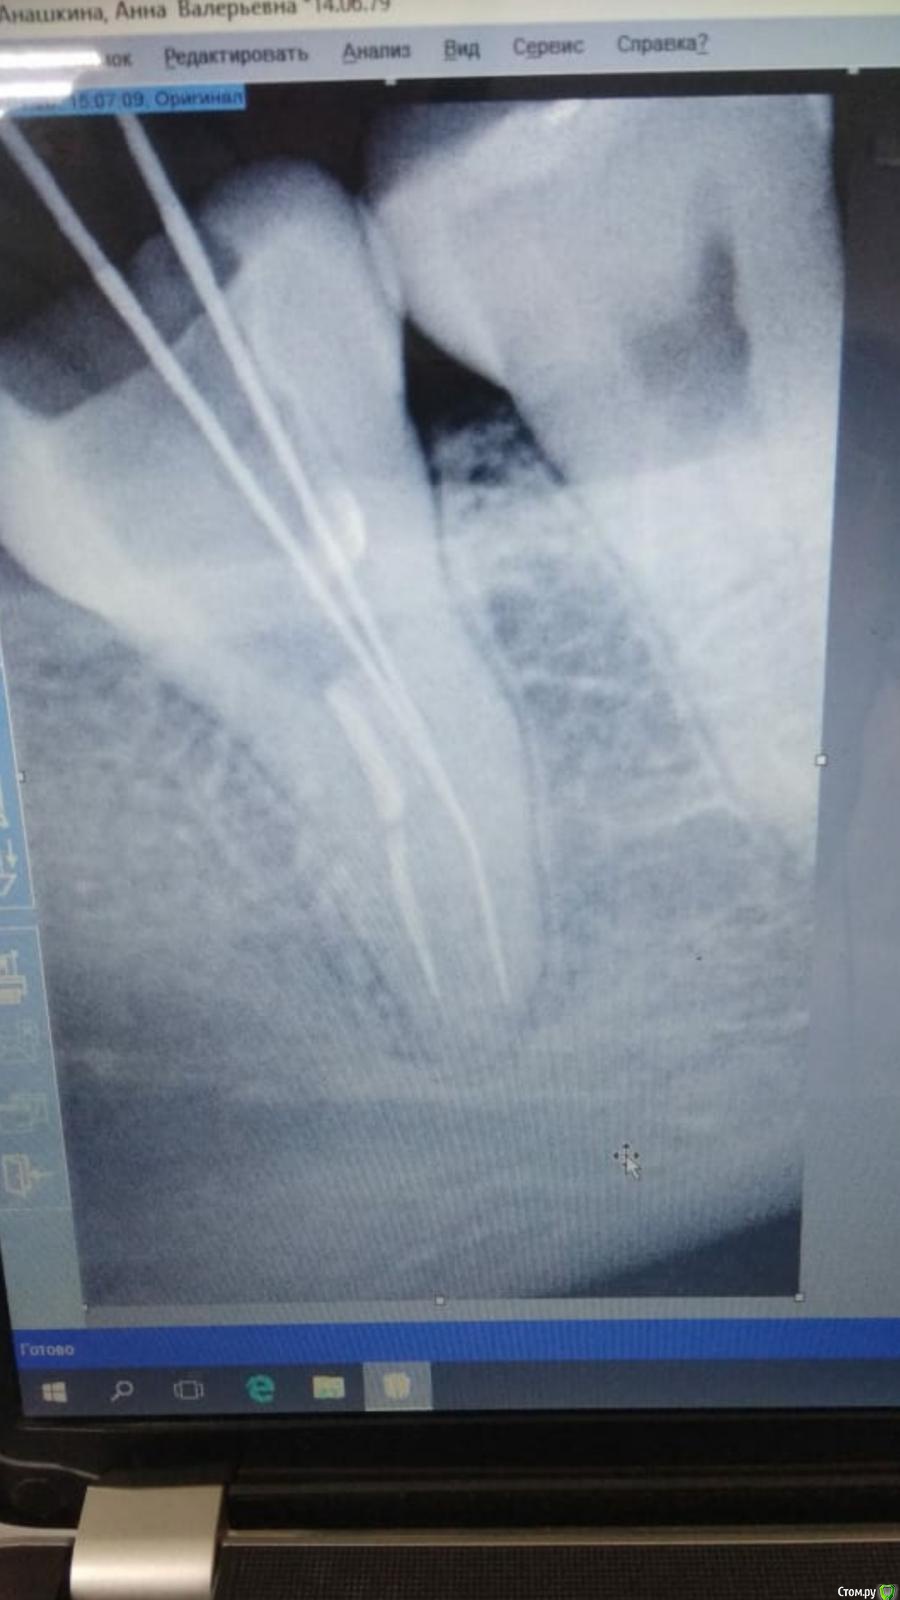

enka Опубликовано 30 января, 2020 Автор Поделиться Опубликовано 30 января, 2020 Извините, но это опять я) Моя подруга плачет, очень не хочет в 30 лет потерять этот зуб. Пожалуйста, посмотрите прицельный снимок, на нем прочищен правый канал, левый еще не тронут. Может если доктор прочистит и его будет все ок? Но он не эндодантист( Зуб начинает ныть к вечеру и ночью, на утро становится легче...Есть надежда хоть маленькая? Ссылка на комментарий

enka Опубликовано 30 января, 2020 Автор Поделиться Опубликовано 30 января, 2020 Другой врач предположил, что причиной нытья может быть семерка. Вскрытие покажет говорит, но это ж не дело(( Ссылка на комментарий